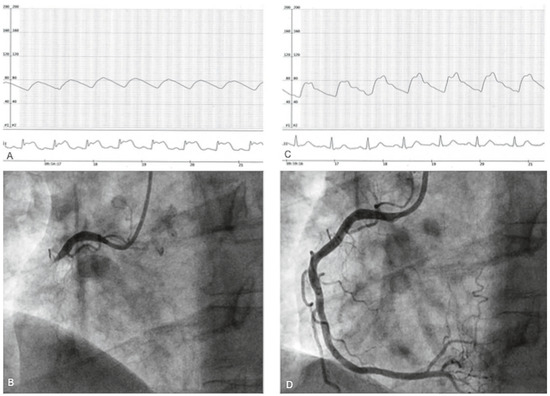

Live Coronary Occlusion During Coronary Angiography

by Caroline Frangos and Stéphane Noble

A 50-year-old man, hypertensive and an active smoker, had for many years been complaining of typical chest pain, which occurred most often upon wakening in the morning [...] Full article

Show Figures

Figure 1